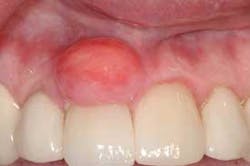

Notes and findings: The patient is a 51-year-old white female maintenance patient who has not had a dental appointment in over two years. She scheduled an appointment because a large growth is noticeable in the anterior region of her mouth, and this lesion has her concerned. The patient reports that the growth has been there for over one year and has grown considerably during that time. As the oral tissues are assessed, it is noted that the large lesion in the anterior is firm, smooth, and sessile (broad-based). The patient reports no pain, but does report that the growth can become somewhat ulcerated if she brushes too hard or traumatizes the area (see Figure 1).

Perioral and intraoral characteristics: The lesions are normally found on the attached gingiva. The abundance of tissue is usually the same color as the surrounding tissue, with a smooth surface. Sometimes the surface may be more textured, depending upon the existing oral forces and location in the patient’s mouth. Additionally, the surface epithelium may be more of a dark color depending upon the amount of trauma and inflammation that is produced with the lesion.